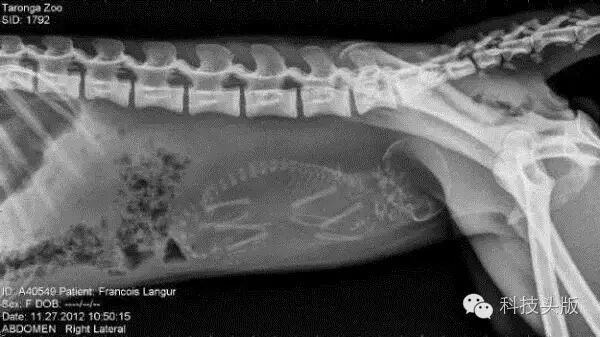

怀孕的猴子。真的不是人宝宝?有点神似啊......